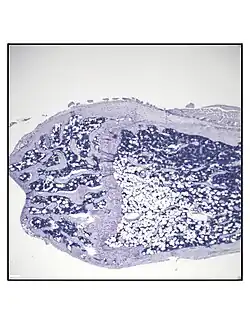

O Tecido Adiposo da Medula Óssea (TAMO), também referido como Tecido Adiposo da Medula (TAM), é um tipo de tecido adiposo (depósito de gordura) encontrado dentro da medula óssea.

Os adipocitos da medula óssea (BMAds) [9] têm origem de progenitoras de células-tronco mesenquimais (MSC) que também dão origem aos osteoblastos, entre outros tipos de células.[10] Por conseguinte, pensa-se que o TAMO resulta da diferenciação preferencial das Células Estaminais Mesenquimais (MSC) na linhagem dos adipócitos, em vez da linhagem dos osteoblastos, no contexto da osteoporose. Uma vez que o TAMO aumenta no contexto da obesidade,[11][12][13] e diminui através de exercícios de resistência,[14][11][15][16] ou vibração,[17] é provável que a fisiologia do BMAT, no cenário do input/exercício mecânico, se aproxime do tecido adiposo branco (WAT).